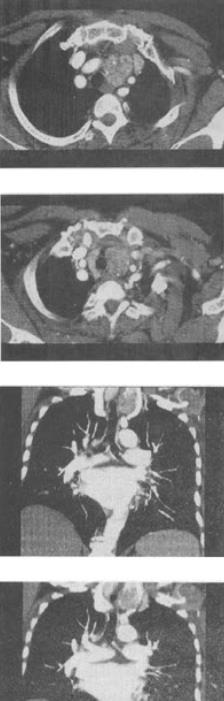

患者女,40岁,发现颈部肿块,随吞咽上下移动,触之无搏动,咳嗽、气喘1周,结合CT检查,最可能的诊断是()。

A、胸腺瘤

B、胸内甲状腺瘤

C、无名动脉瘤

D、无名动脉伸展扭曲

E、淋巴瘤

B